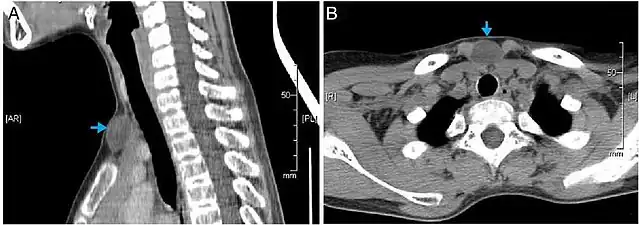

Kyste épidermique de la nuque inflammé

Les kystes épidermiques sont généralement diagnostiqués lorsqu'une personne remarque une bosse sur la peau et consulte un médecin. Le diagnostic définitif est posé après exérèse, par un médecin pathologiste sur la base de l'aspect microscopique d'une lésion kystique bordée d'un épithélium malpighien contenant de la kératine lamellaire[5]. Ils peuvent également être observés sous forme de lésions isointenses en IRM ou d'hyperintensités en FLAIR.